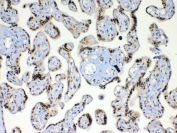

IHC testing of FFPE human placental tissue with XRCC1 antibody at 1ug/ml. Required HIER: steam section in pH6 citrate buffer for 20 min and allow to cool prior to testing.